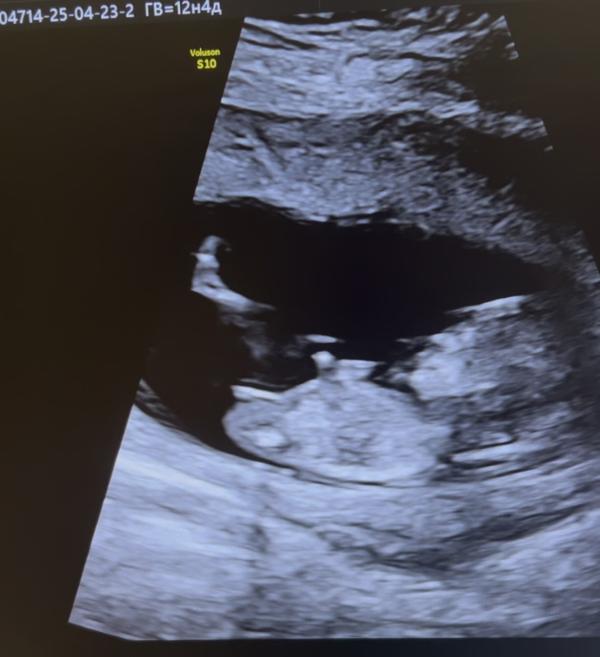

Как думаете девочка или мальчик ? Срок по скринингу 12,2

Читала если угол больше 30% то мальчик ,если более прямой девочка )

Кто нибудь разбирается?)заранее спасибо

@ma_an4ik, хотя знаете что,я видела у одного блогера видео точно такой же бугорок как увас,но унее был мальчик